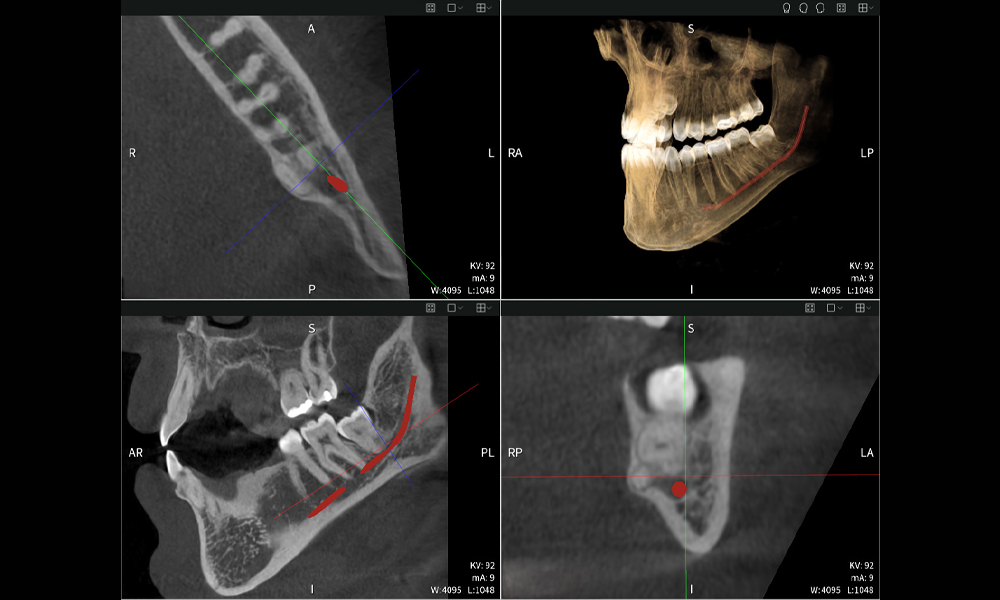

Figures b–d show various views of a 3D reconstruction of the mandible, providing a comprehensive overview of the mandibular anatomy, the position of the nerves in relation to the teeth, and allowing assessment of tooth symmetry and alignment.

Figure e: The panoramic X-ray serves as an initial assessment tool, showing the general positioning of the teeth as well as any potential pathological changes. Notably, on the right side (tooth 48), the situation following a crown amputation performed by an external practitioner is visible. The two severely curved roots remain in close topographical proximity to the inferior alveolar nerve within the bone. This suggests a deliberate decision to avoid the increased risk of nerve injury during a complete extraction, and represents a clinically relevant finding. In summary, CBCT scans with Seethrough Max, provide crucial information about the complex anatomy and the critical relationship between the wisdom teeth and the inferior alveolar nerve. This detailed preoperative diagnostic imaging is essential for safe and successful surgical procedures in the mandibular region.